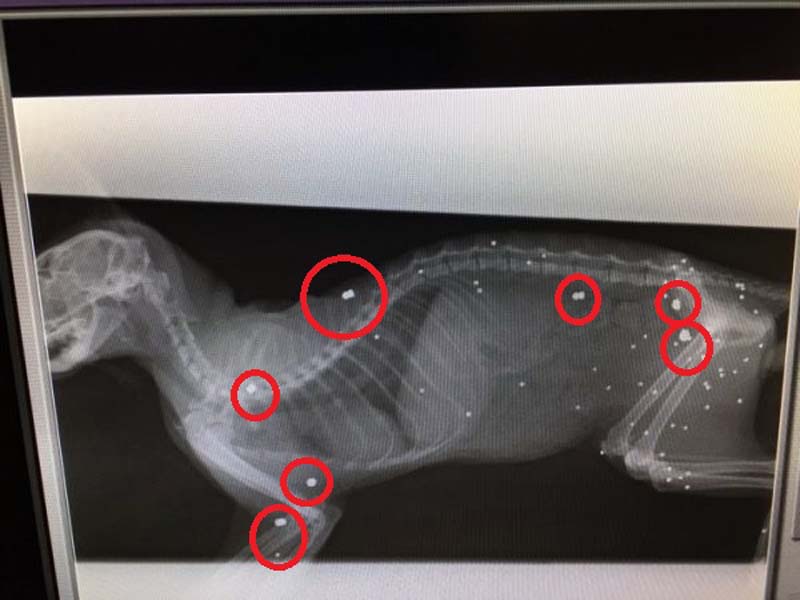

Ο Φιλοζωικός Σύλλογος Χανίων «Η ΠΡΟΣΤΑΣΙΑ ΤΩΝ ΖΩΩΝ» έφερε στη δημοσιότητα ακόμα ένα έγκλημα εις βάρος γάτας που συνέβη στο χωριό Βατόλακκος Χανίων στην Κρήτη. Η γάτα, που αν και βρέθηκε ετοιμοθάνατη στις 26 Δεκεμβρίου 2017, τελικά επέζησε, εντοπίστηκε με κρανιοεγκεφαλικές κακώσεις, με σπασμένη γνάθο ενώ οι ακτινογραφίες που έγιναν σήμερα έδειξαν ότι έχει δεκάδες σκάγια καραμπίνας στο κορμί της αλλά και πολλά σφαιρίδια αεροβόλου ένα εκ των οποίων είναι καρφωμένο στο κεφάλι της και προφανώς αυτό οδήγησε και στην τύφλωση της…

Δεκάδες σκάγια στο σώμα του ζώου που πυροβολήθηκε με καραμπίνα και αεροβόλο.

Δεκάδες σκάγια στο σώμα του ζώου που πυροβολήθηκε με καραμπίνα και αεροβόλο.

Ένα από τα μεταλλικά σφαιρίδια καρφωμένο στο κεφάλι του ζώου.

Ένα από τα μεταλλικά σφαιρίδια καρφωμένο στο κεφάλι του ζώου.

Επειδή δεν υπήρχε ακτινογραφία, αναλάβαμε τα περαιτέρω έξοδα και το ζώο μεταφέρθηκε στο κτηνιατρείο Καμπουράκη - Βαλυράκη, όπου από τις ακτινογραφίες διαπιστώθηκε ότι όλο το κορμάκι της ήταν διάτρητο από σκάγια, ενώ υπήρχε και ένα καρφωμένο ανάμεσα στα μάτια, που πιθανότατα προκάλεσε την τύφλωση στο άτυχο ζώο.